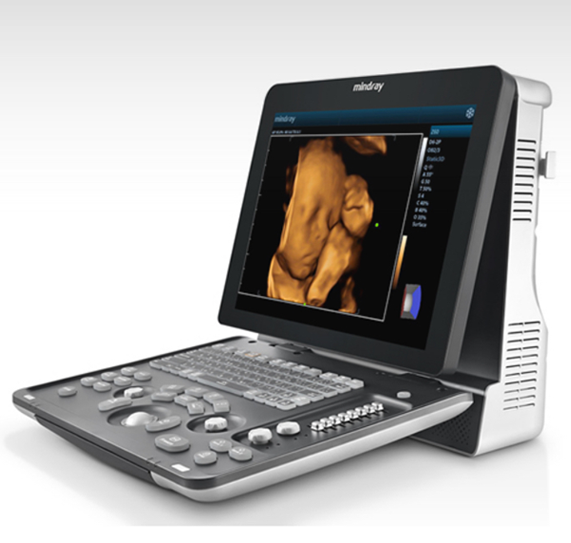

Z60

Sistema de diagnóstico ecográfico.

El sistema Z60 es una buena opción para aquellos que requieren un rendimiento de imagen de alta calidad, una movilidad simple y asequibilidad cuando se trata de imágenes ecográficas avanzadas. Con configuraciones completas y un diseño integrado, el Z60 es el resultado de los esfuerzos continuos y decididos de Mindray para hacer que la atención médica primaria sea más eficiente, eficaz y accesible para todos.